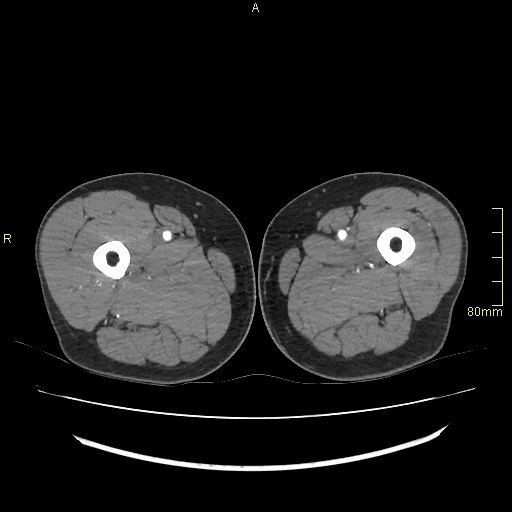

CT Angiography Lower Limb (Knees down) - Soft tissue window (axial)

CT Angiography Lower Limb (knees down)- Soft tissue window (coronal)

CT Angiography Lower Limb (knees down)- Soft tissue window (sagittal)